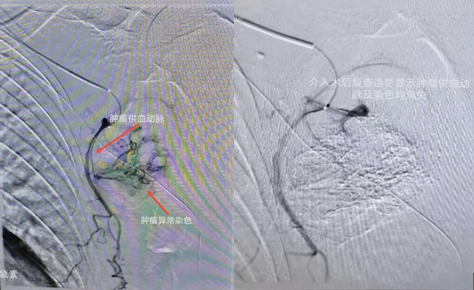

介入術(shù)中圖片

近日,吉林國文醫(yī)院淋巴瘤科與介入一科相互合作,成功為一例皮膚惡性黑色素瘤患者,實施了實體腫瘤動脈灌注化療栓塞術(shù),患者李某某10個月前曾確診為皮膚惡性黑色素瘤,腫瘤分布在左側(cè)腋下,患者既往曾多次行靜脈化療及免疫治療,但腫瘤病情仍然繼續(xù)進展,患者目前左側(cè)腋下腫瘤病灶增長較快,伴有局部脹痛感,淋巴瘤科左淑波主任綜合分析患者病情后,邀請介入一科韓長清主任進行共同商討治療方案,評估是否可行介入手術(shù)治療,經(jīng)兩位主任共同商討后決定,可給予患者行腫瘤供血動脈化療栓塞術(shù)介入治療。介入術(shù)中非常順利,成功尋找到腫瘤供血動脈并給予治療,術(shù)后患者恢復(fù)良好,疼痛癥狀有所改善。